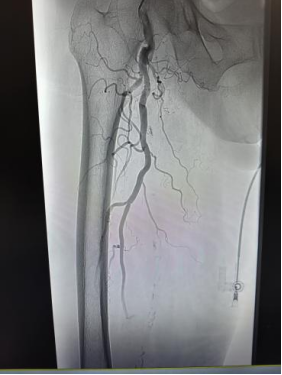

患者今年94岁,因下肢发凉、麻木、疼痛、行走困难前来就诊,经详细检查确诊为下肢动脉闭塞。患者病情进展快、肢体缺血,若不及时疏通血管,将面临下肢坏死、截肢甚至危及生命的风险。但超高龄患者往往伴随心肺功能减退、手术耐受差等多重难题,手术风险高,治疗难度极大。

面对严峻病情与家属的殷切期盼,血管外科团队高度重视,联合老年医学科、康复医学科、重症医学科等多学科进行周密会诊评估,反复研判手术方案,精准把控手术指征与风险节点,制定出个体化手术方案。在充分术前准备与严密术中监护下,手术团队凭借精湛技术,为患者开通闭塞血管,恢复下肢血供。